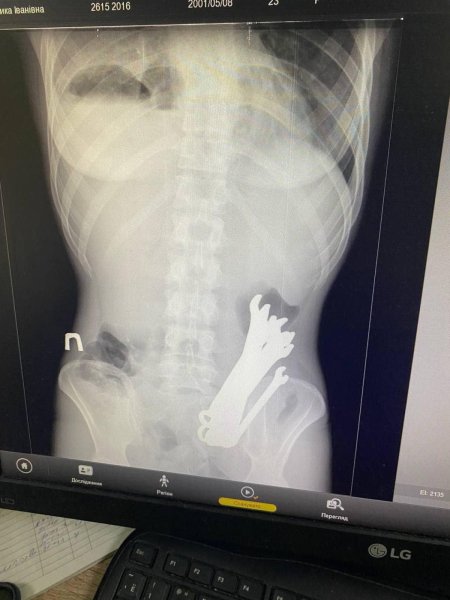

У Черкасах медики рятували чоловіка, який потрапив до лікарні у важкому стані. Рентген показав, що у шлунку пацієнта сторонні залізні предмети. Про це повідомили у відділенні торакальної хірургії Черкаської обласної лікарні.

Медики лікарні провели операційне втручання і дістали з тіла пацієнта 6 гайкових ключів. Після трьох тижнів лікування його виписали з медзакладу. Яким чином інструменти опинилися у шлунку чоловіка – не повідомляється.